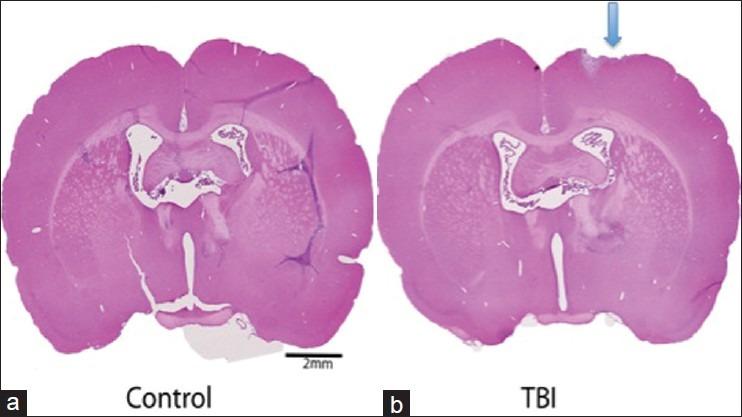

NSS-R scores of TBI rats (5.4 ± 0.5) in comparison to naïe rats (3.9 ± 0.5) and H and E staining of brain sections suggested a mild brain injury. Bioinformatics and systems biology analyses showed 31 dysregulated genes, 10 affected canonical molecular pathways including a number of genes involved in mitochondrial enzymes for oxidative phosphorylation, mitogen-activated protein Kinase (MAP), peroxisome proliferator-activated protein (PPAP), apoptosis signaling, and genes responsible for long-term potentiation of Alzheimer's and Parkinson's diseases.